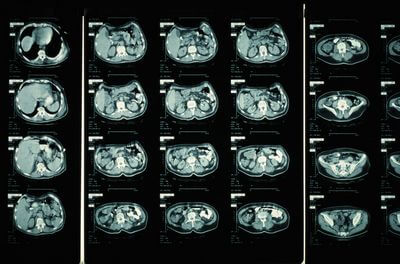

Перш ніж зануритися в деталі того, що можна побачити на КТ-скані, важливо зрозуміти, як працює КТ-сканування. Під час КТ пацієнт лежить на столі, який рухається через машину у формі пончика, що називається комп’ютерним томографом. Сканер використовує рентгенівські промені для створення зображень поперечного перерізу тіла, які потім обробляються комп’ютером для створення детальних 3D-зображень.

Комп’ютерна томографія дозволяє отримати багато інформації про внутрішні структури організму. Деякі з речей, які можна побачити на КТ, включають в себе:

КТ – це універсальний діагностичний інструмент, який можна використовувати для діагностики та моніторингу широкого спектру захворювань. Деякі з найпоширеніших застосувань КТ включають:

КТ – це потужний діагностичний інструмент, який може розкрити багато інформації про внутрішні структури організму. Вони особливо корисні для оцінки м’яких тканин і виявлення аномалій, які можуть бути невидимі на звичайних рентгенівських знімках. КТ можна використовувати для діагностики та моніторингу широкого спектру захворювань, включаючи рак, травми, неврологічні розлади, а також біль у грудях та животі.